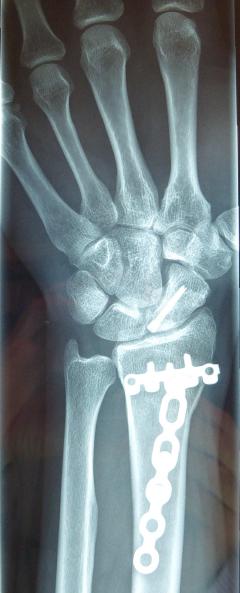

Η αντιμετώπιση της ψευδάρθρωσης του σκαφοειδούς είναι πάντοτε χειρουργική. Με ραχιαία ή παλαμιαία προσπέλαση αποκαθίσταται ο άξονας του σκαφοειδούς και σταθεροποιείται το σκαφοειδές με ειδική βίδα ή βελόνες, με παράλληλη τοποθέτηση οστικών μοσχευμάτων. Μπορεί επιπλέον να γίνει και οστεοτομία κλειστής σφήνας του περιφερικού άκρου της κερκίδος. Στις περιπτώσεις άσηπτης νέκρωσης το μόσχευμα πρέπει να είναι αγγειούμενο – για να προσδώσει αιμάτωση στο νεκρωμένο κεντρικό τμήμα – και λαμβάνεται με μικροχειρουργικές τεχνικές από το περιφερικό τμήμα της κερκίδος ή από άλλα τμήματα του σώματος

Μετεγχειρητικά 1

Μετεγχειρητικά 2